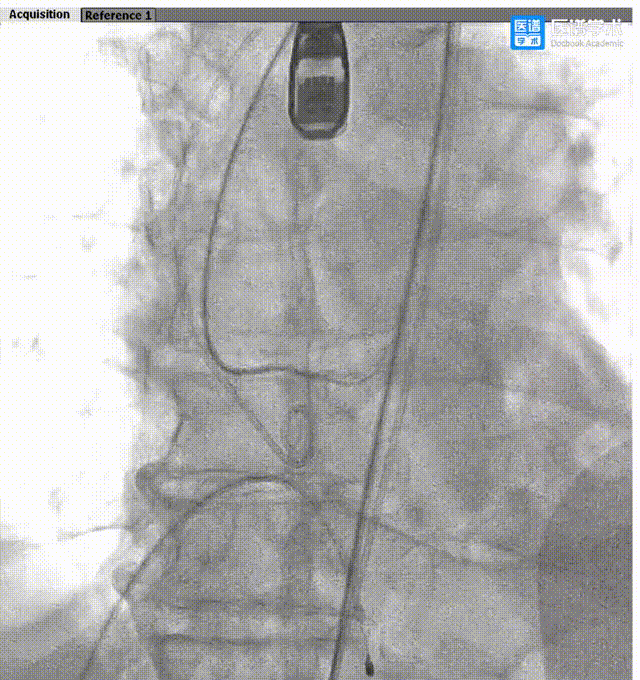

手术过程概览:

导丝轻松跨瓣

Taurus输送器柔顺的姿态,过弓不伤弓

瓣膜释放,彰显配合精准